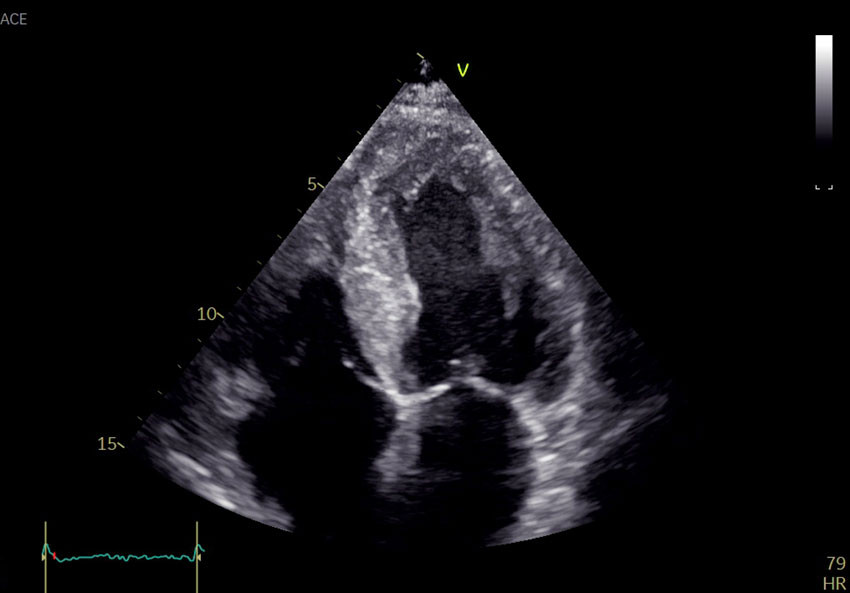

Grunnet de ekkokardiografiske funnene henviste behandlende lege til skjelettscintigrafi med technetiummerket 3,3-difosfono-1,2-propanodikarboksylsyre (99 mTc-DPD), som ble utført fem dager senere, mens pasienten var inneliggende. Det ble også tatt prøver til urin- og serum-proteinelektroforese. Skjelettscintigrafi avdekket høyt DPD-opptak i hjertet, Perugini-grad 2 (figur 2). Proteinelektroforese avdekket monoklonal komponent (M-komponent) bestående av IgA-kappa. Det var forhøyede frie kappa-kjeder (850 mg/L (4–25)) og frie lambda-kjeder (33 mg/L (6–27)). Kappa/lambda-ratioen var 25,8 (0,5–1,6), klart patologisk.

Skjelettscintigrafi er en nukleærmedisinsk undersøkelse som brukes ved mistanke om patologiske tilstander i skjelettet, for eksempel metastaser. 99 mTc-DPD-scintigrafi har vist seg å ha svært god diagnostisk nøyaktighet for kardial ATTR-amyloidose, forutsett at AL-amyloidose er utelukket gjennom urin- og serum-proteinelektroforese (4). DPD-opptaket i myokard graderes etter Peruginis skala fra 0 til 3, avhengig av hvor stort opptaket i myokard er sammenliknet med skjelettet. Grad 2–3 sees typisk ved ATTR-amyloidose (5). Ved AL-amyloidose ses som oftest intet (grad 0) eller lett økt opptak (grad 1), men grad 2–3 ekskluderer ikke AL-amyloidose (4). Flere bifosfonater, for eksempel hydroksydifosfat og pyrofosfat, kan også brukes for å påvise hjerteamyloidose.

Det kraftige DPD-opptaket i hjertet var forenlig med ATTR-amyloidose. Ettersom pasienten hadde påvist M-komponent og avvik i kappa/lambda-ratioen, måtte AL-amyloidose utelukkes. Benmargsbiopsi ble tatt tre uker senere ved lokalsykehuset, og pasienten ble henvist til et annet regionssykehus for høyresidig hjertekateterisering og hjertebiopsi. Høyresidig hjertekateterisering ble utført fire uker senere og avdekket middeltrykk i arteria pulmonalis på 22 mmHg (< 20) og litt lavt minuttvolum på 4,6 L/min (> 5). Biopsier fra septum ble sendt til histopatologisk undersøkelse.